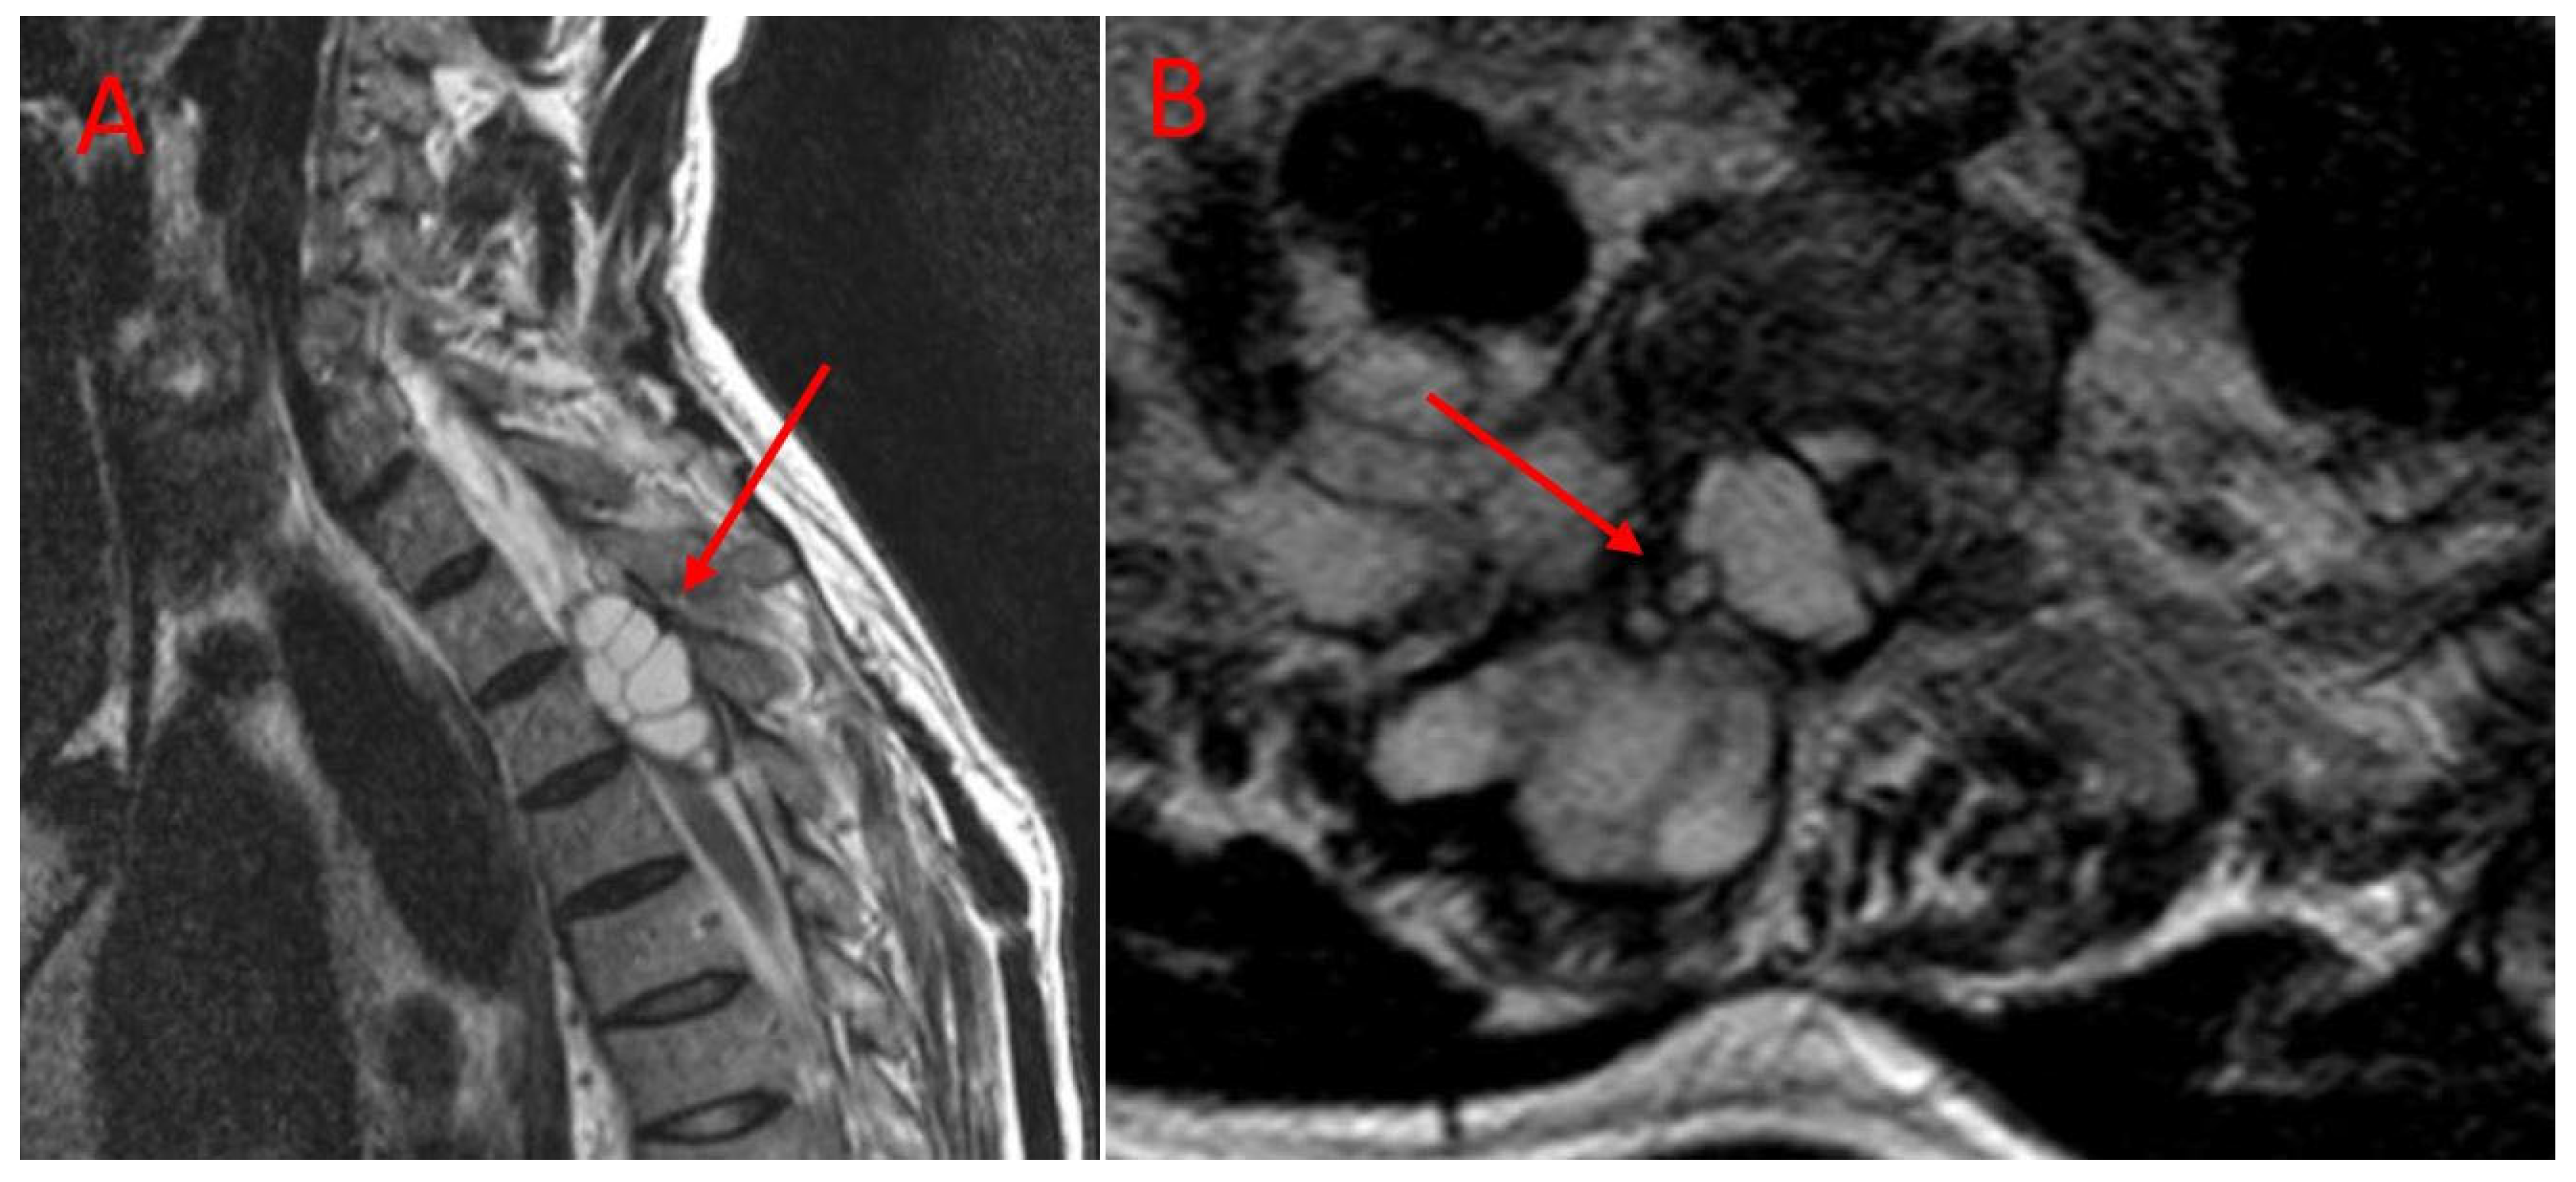

Imaging studies revealed that the lesions involved multiple anatomical structures within the vertebral segment. All the patients in the TES group exhibited vertebral body involvement, while the CLDS patients did not present any corpus involvement (p < 0.001). Posterior element involvement was universal in the CLDS group and was also common in TES patients. Paravertebral extension was noted in both groups. Major spinal canal invasion (>50%) was observed in both groups (Table 2). Representative MRI and CT images are provided in Figure 4 and Figure 5.

Figure 4. Preoperative T2-weighted MR images of a patient treated with CLDS. (A): The arrows indicate multilocular hydatid cysts invading the spinal canal. (B): The arrows indicate hydatid cysts (shown from an axial perspective) with a unilateral location extending into the spinal canal and paravertebral muscles.